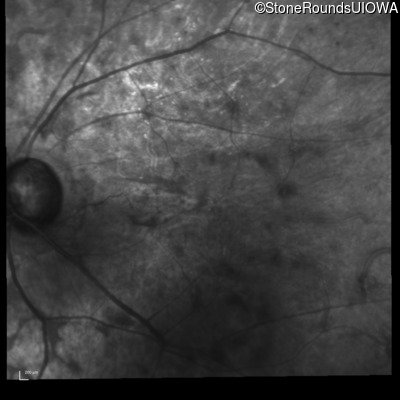

Infrared Fundus Photograph - Left - 20/80 -1

Exemplar